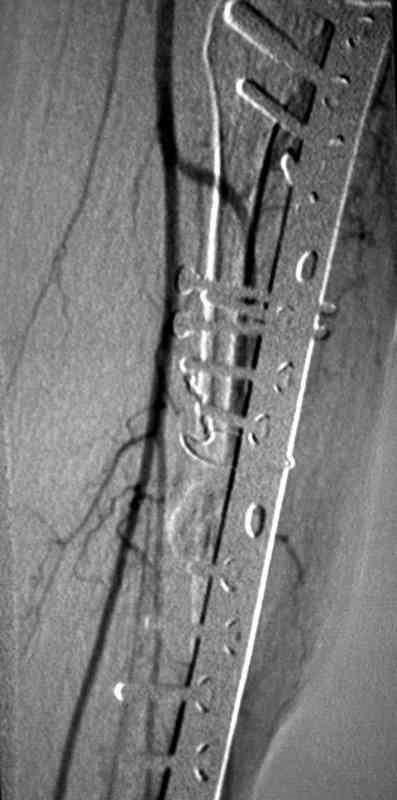

Вторым этапом можно приступить к восстановлению на кости, это может быть сделано аппаратом Илизарова с иссечением концов костей с дальнейшими удлинениями или доступными интра, экстра-медуллярными методами. У нас тоже похожий случай, коллега пластический хирург помог мне, больной после 13 операций на голени,

инфицированный с металлоконструкцией ложный сустав

ангиография,

взятие вены сафенус и подключение к popliteal artery,

rectus muscular flap

вид в аппарате

и окончательный вид.